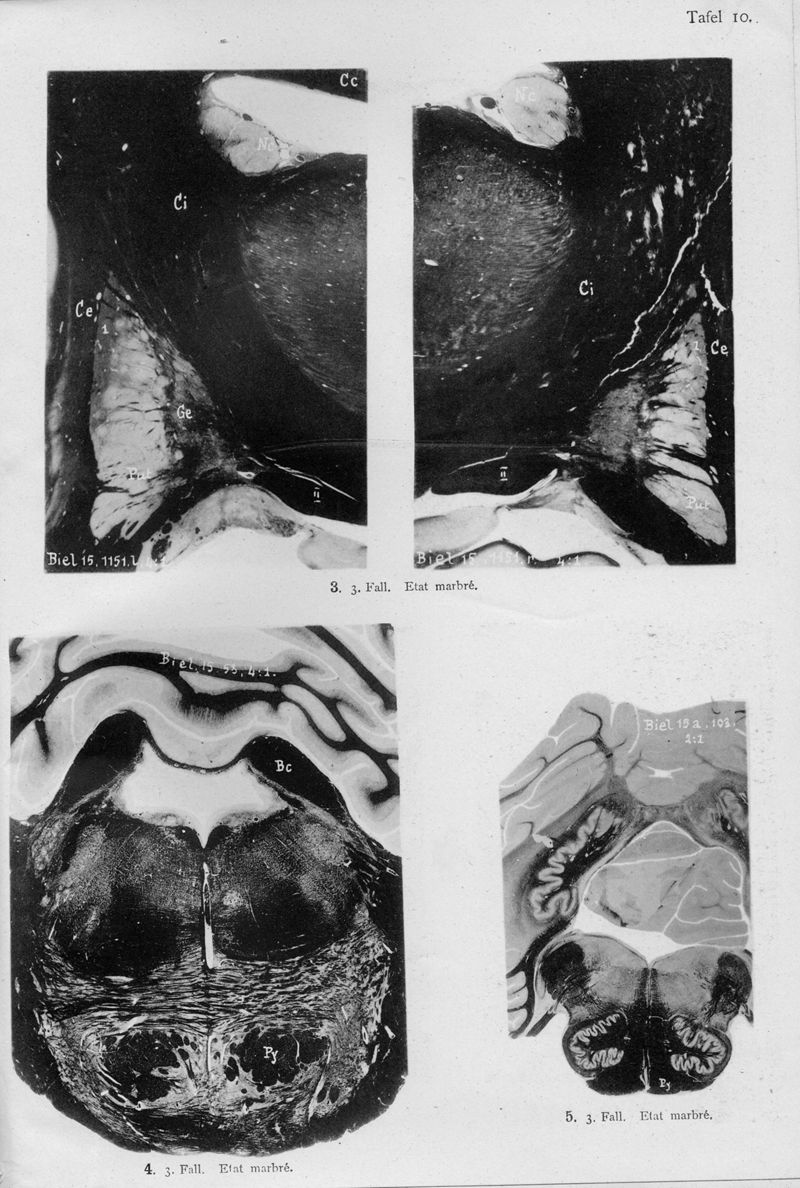

VOGT, Cécile / VOGT, O.

In : Journal für Psychologie und Neurologie,

1920, Vol. 25, pp. 627-846